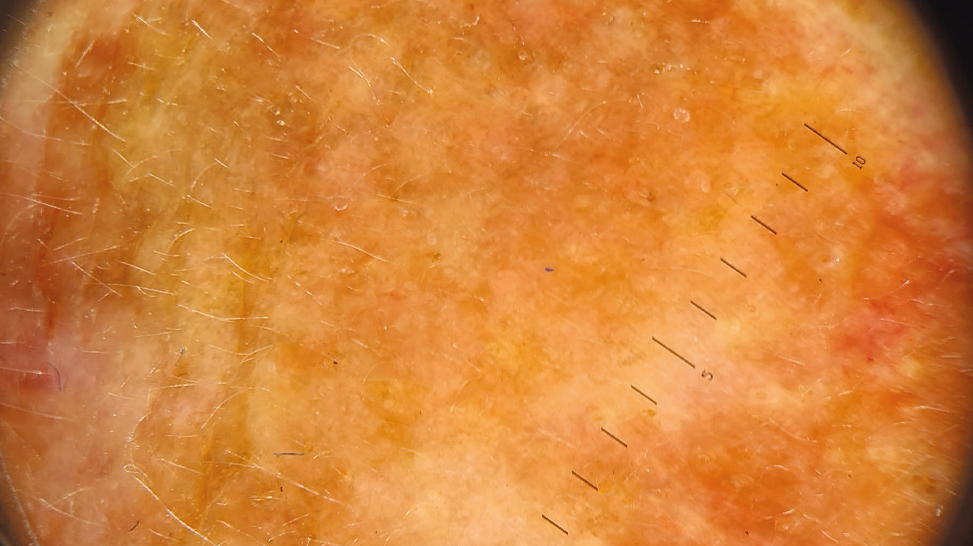

Dermoscopy of the upper eyelid area showed the homogeneous structure of the lesion, uneven distribution of brown pigment, pale brown/brown areas (Fig. 8).

Fig. 8. Dermoscopy (×10) performed before treatment: homogeneous structure, brown pigment distributed unevenly with areas of pale brown/brown color.

Diagnosis: Congenital combined nevus.